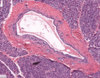

Classical liver lobule - classical liver lobule (outlined by arrowheads) is defined by the arrangement of connective tissue in the portal tract (B) areas and has its centre at the central vein (A) or terminal hepatic venule. Hepatocytes radiate along blood sinusoids from the tracts to the central vein and bile flows in the opposite direction